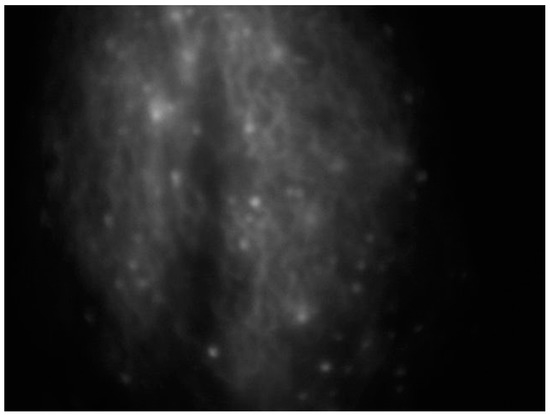

An effective substitute for assessing lymphatics is near-infrared fluorescence imaging, which uses a contrast media injected intradermally instead of a radionuclide to access the primary lymphatics beneath the epidermis, helping to assess lymphatic anatomy and function [38] (Figure 2).

ICG lymphography is performed by injecting this fluorescent dye into the interdigital web spaces; after 4 h, a photodynamic eye camera equipment can be used to capture fluorescence images of lymphatic vessels to a maximum depth of 2 cm; the fluorescence images are digitalized for real-time display [21,41] and can be used also for sentinel lymph node detection in cancer interventions [42].

Figure 2. Intraoperative ICG lymphography for lower limb lymphatic vessel evaluation in a patient with post-prostatectomy secondary lymphedema.